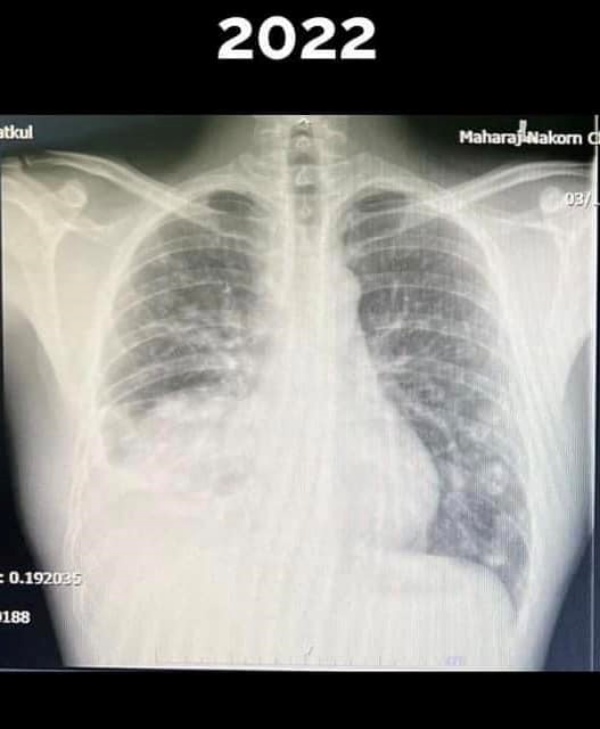

หมอแล็บแพนด้า หรือ ทนพ.ภาคภูมิ เดชหัสดิน นักเทคนิคการแพทย์ กล่าวถึงจากกรณีของ นพ.กฤตไท ธนสมบัติกุล วัย 28 ปี อาจารย์ประจำศูนย์ระบาดวิทยาคลินิกและสถิติศาสตร์คลินิก ภาควิชาเวชศาสตร์ครอบครัว คณะแพทย์ศาสตร์ มหาวิทยาลัยเชียงใหม่ ที่แชร์เรื่องราวของตัวเองหลังตรวจเจอมะเร็งปอดระยะลุกลาม หรือระยะสุดท้าย ทั้งๆที่ร่างกายแข็งแรงปกติดีทุกอย่าง รักสุขภาพไม่สูบบุหรี่ นอนตรงเวลา แต่เมื่อเอกซเรย์ล่าสุดกลับพบว่า ปอดซีกขวาหายไปเกือบครึ่งหนึ่ง พร้อมยกเรื่องของฝุ่นพิษ pm 2.5 ขึ้นมาพูดถึงอีกครั้ง โดยโพสต์ข้อความระบุว่า

มลพิษทางอากาศและ PM 2.5 ถูกกลับมาพูดถึงอีกครั้งครับ เพราะหมอหนุ่มที่ออกกำลังสม่ำเสมอ เล่นกีฬา กินคลีน ไม่สูบบุหรี่ ดื่มน้อยมาก ทำงานไม่เครียด นอน เป็นเวลากลับตรวจเจอมะเร็งปอดระยะลุกลาม ปอดขวาหายไปครึ่งนึงแล้ว